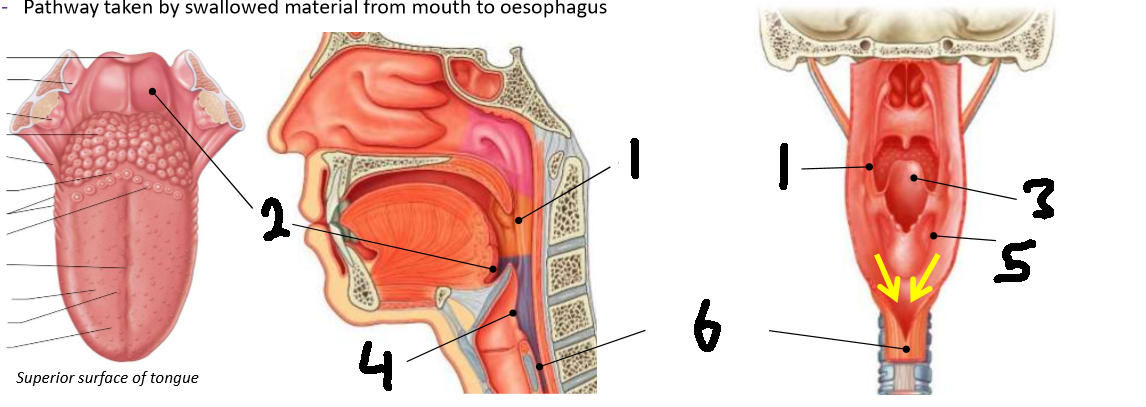

What is 1?

palatopharyngeal arch

What is 2?

vallecula

What is 3?

epiglottis

What is 4?

laryngeal inlet

What is 5?

piriform fossa

What is 6?

oesophagus